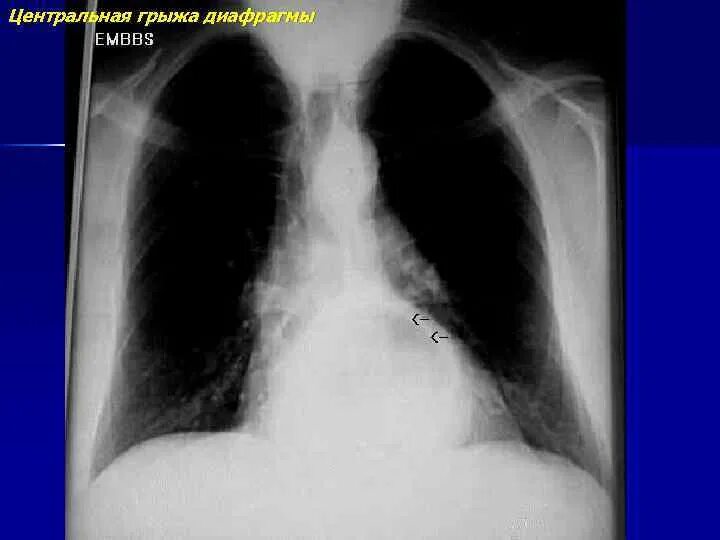

Диагностика диафрагмальной грыжи